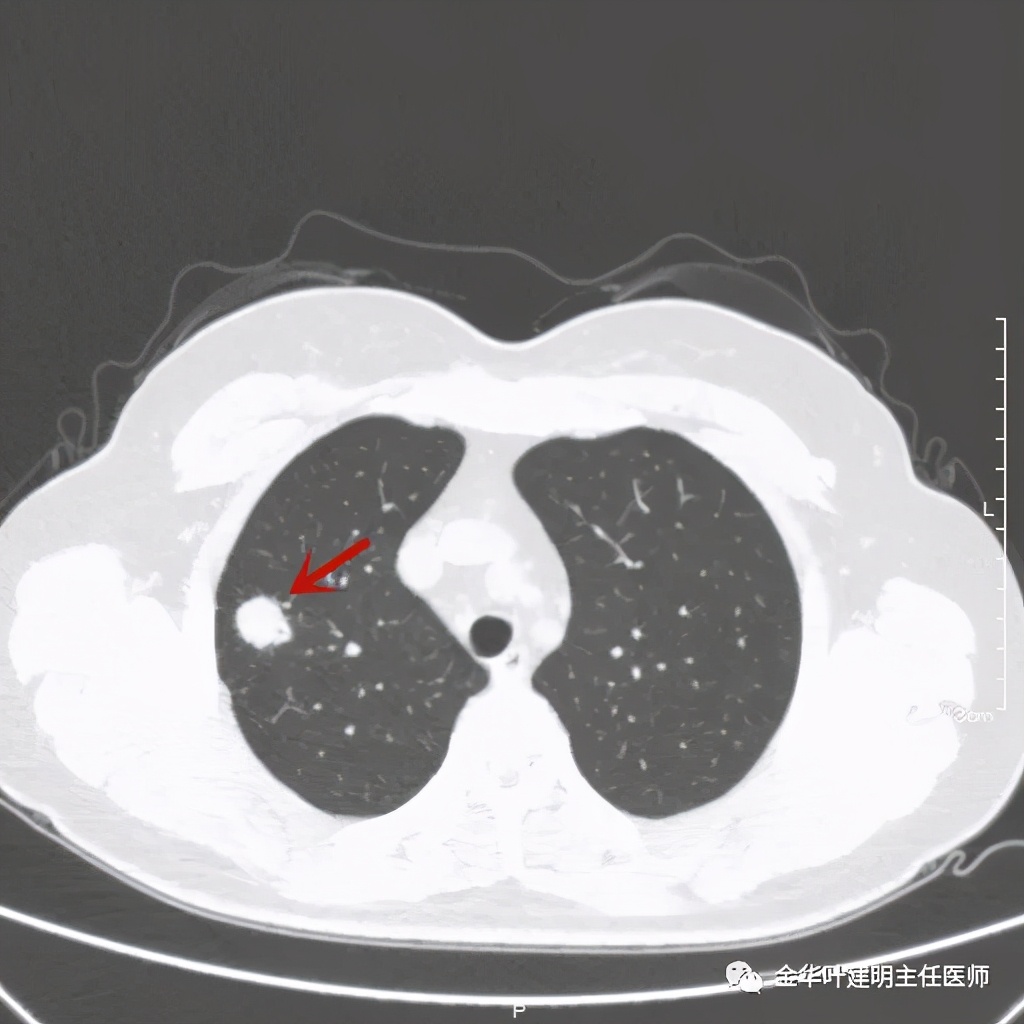

右上叶开始出现病灶,是实性的

病灶比较光滑,密度高,旁边有小的卫星灶,不清爽